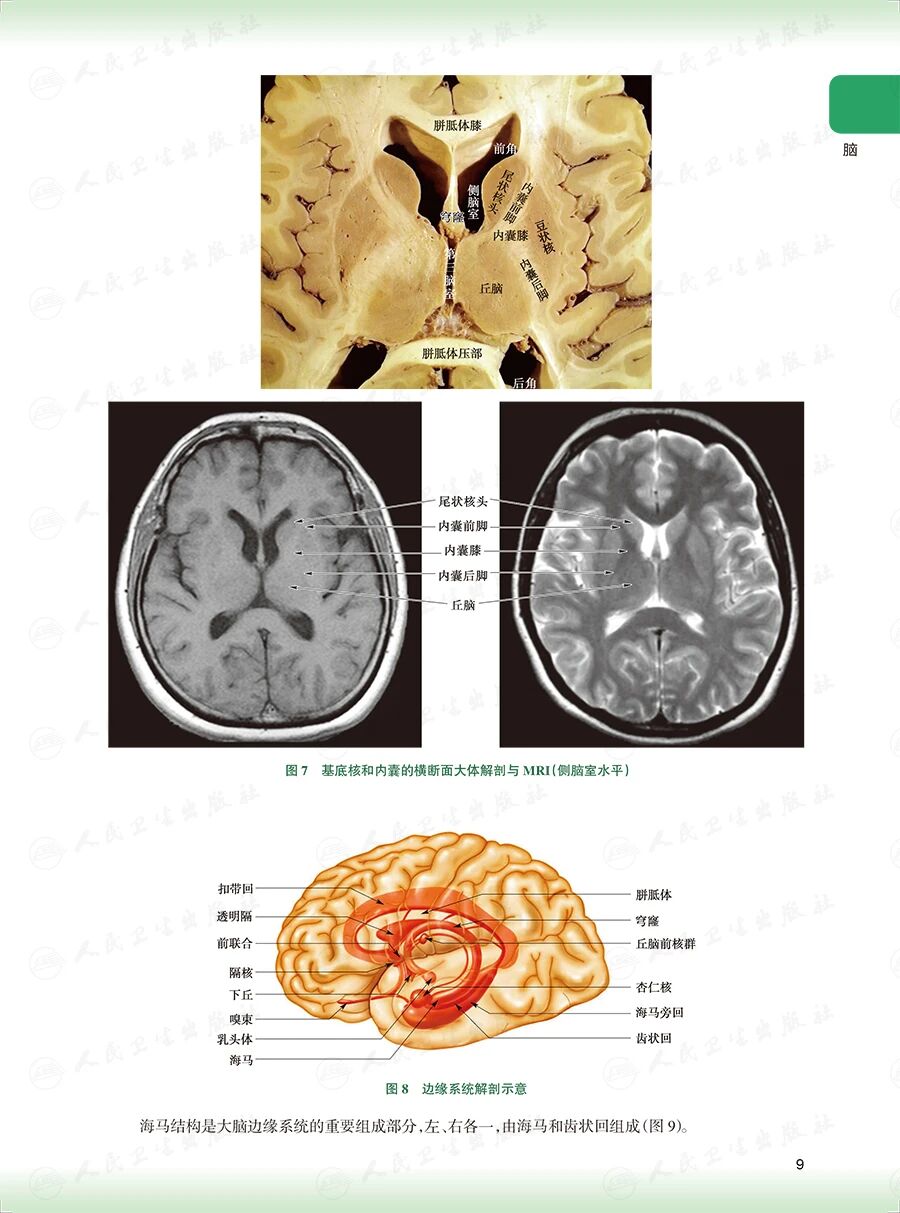

《头颈部放射治疗解剖图谱》

——破译头颈部靶区勾画的解剖密钥

样章试读